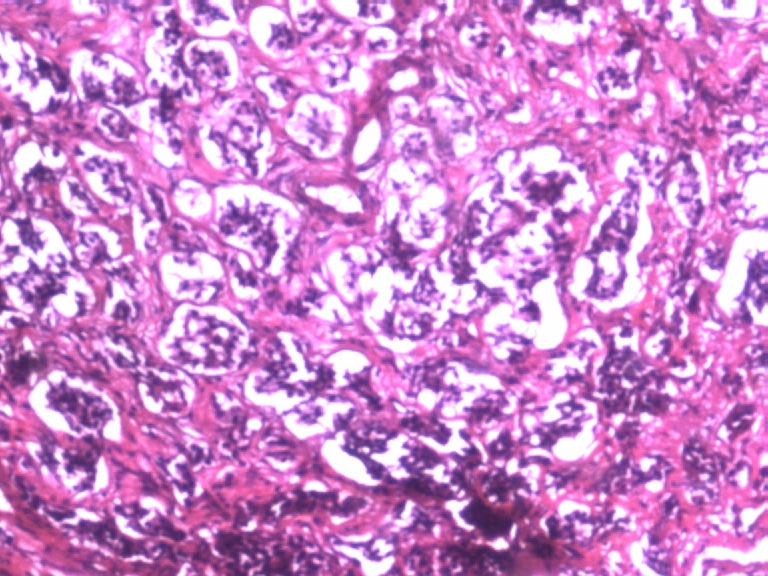

男,50岁,阑尾长7厘米,直径0.4---0.6厘米。剖开:尖端看见淡黄色区,不规则,界限欠清,0.15*0.2厘米,质中。

×参考诊断

考虑阑尾类癌

像类癌,有些粘液,标记一下Syn、CgA,有可能是杯状细胞类癌

按照胃肠胰腺神经内分泌肿瘤WHO2010分类,该例应属于NET G1(神经内分泌瘤,1级)。需标记Syn, CgA, Ki67.

倾向神经内分泌肿瘤,建议做CgA、SYN、Ki-67检查。

阑尾的神经内分泌肿瘤我们已经碰到好几例了,一般都在阑尾尖端,取材一定要规范,这样可以减少漏诊率。